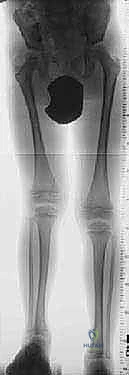

1. التقييم والتخطيط قبل الجراحة (Pre-operative Planning)

يتم إجراء فحص سريري شامل للمريض، متبوعاً بصور أشعة سينية بانورامية (Scanogram) لقياس طول العظام بدقة مليمترية. يقوم الدكتور هطيف باستخدام برامج تخطيط ثلاثية الأبعاد لتحديد نقطة القطع العظمي ونوع الجهاز الأنسب (إليزاروف أم أحادي المستوى).